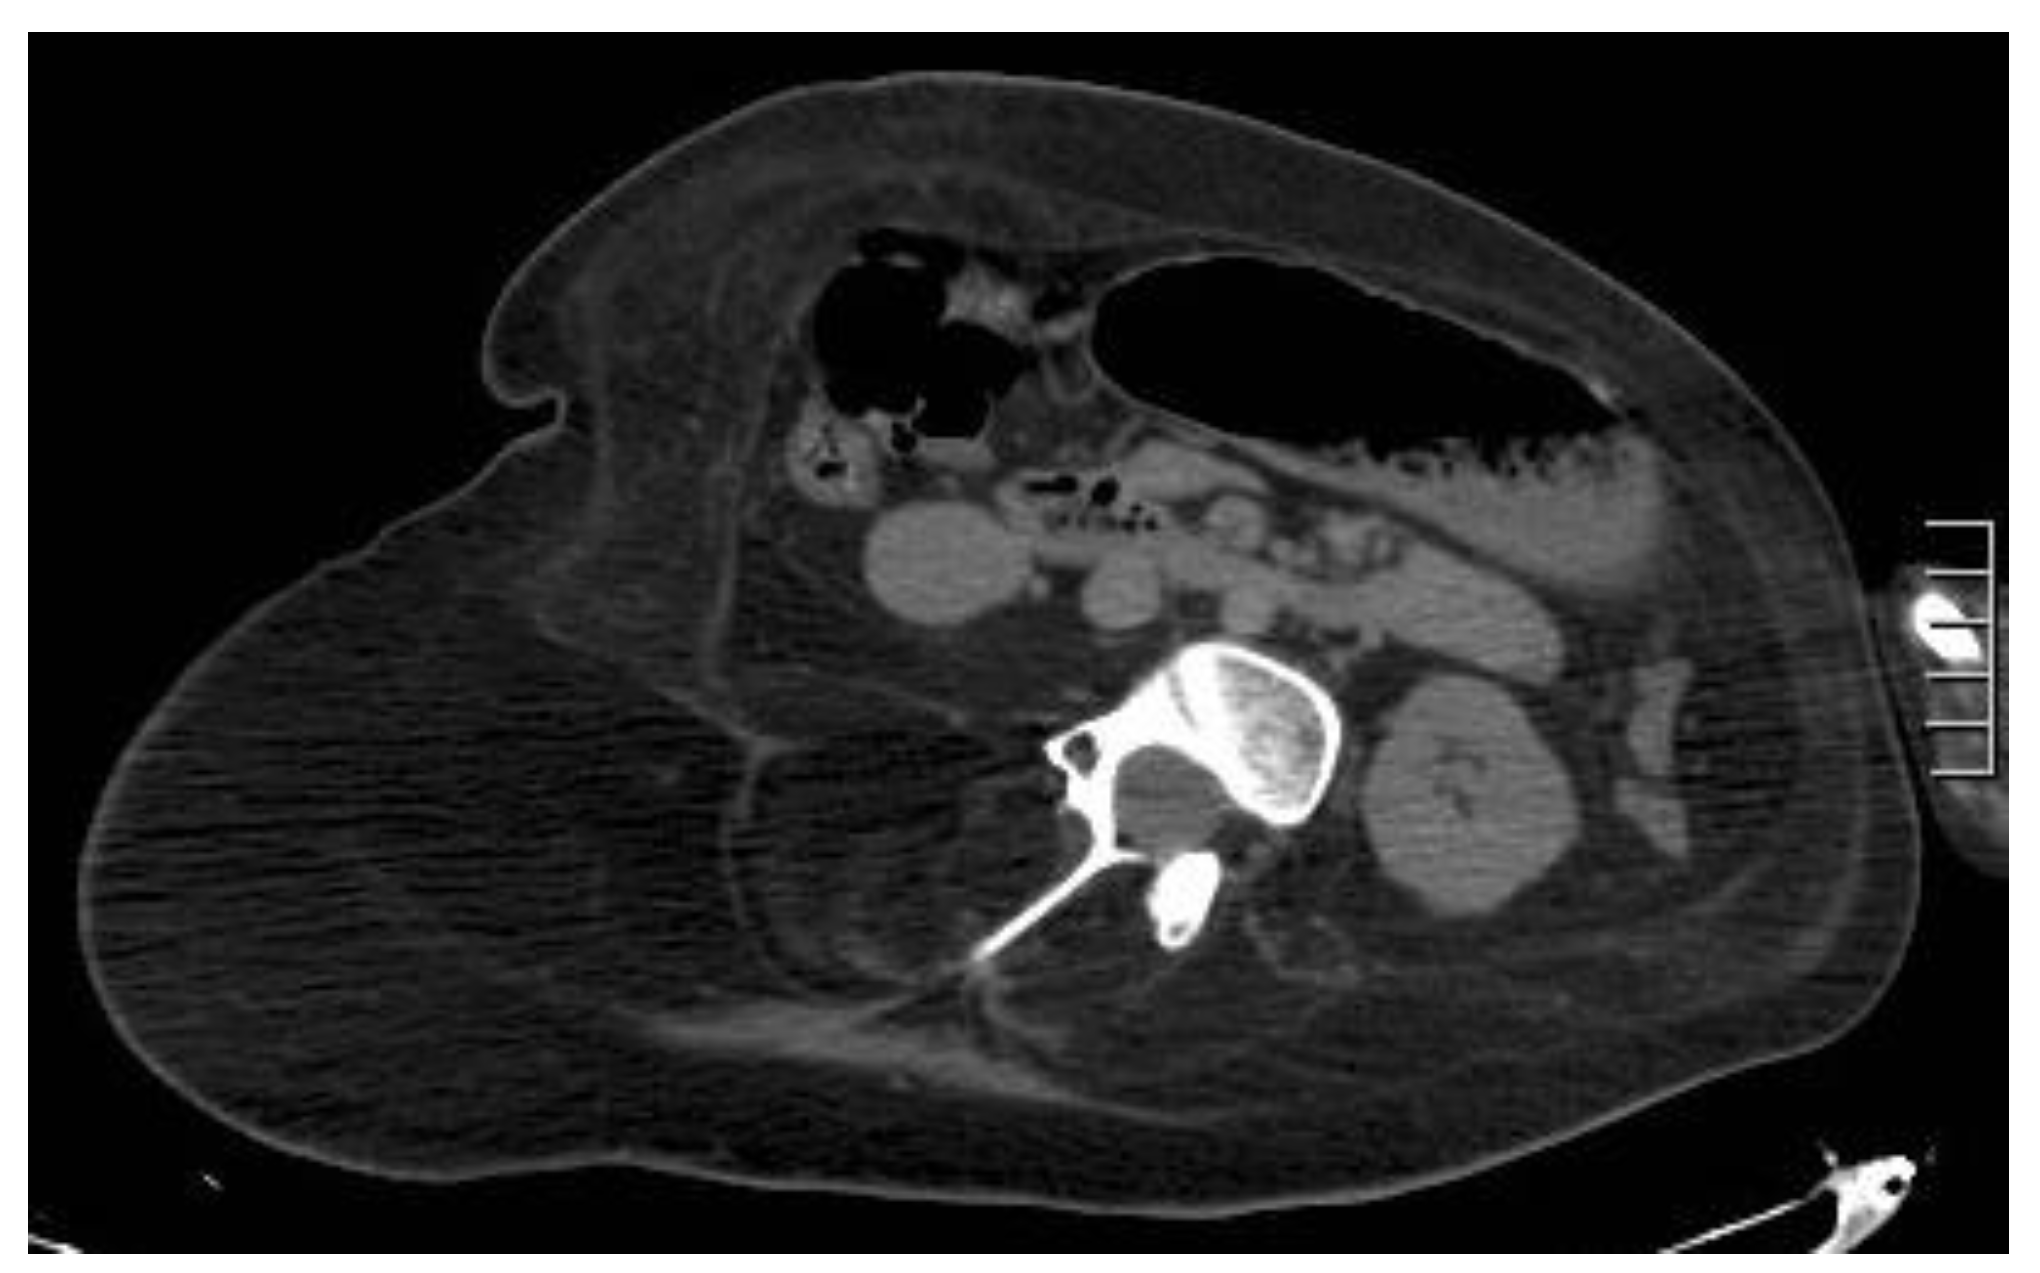

Figure 11. Hematoma below the arcuate line in a 75-year-old woman, with acute myeloid leukemia and low platelet count. After a cough, she started complaining of strong abdominal pain and a mass started growing. Coronal and axial, pre- and post-contrast injection images showed the presence of a large left rectus sheath hematoma (thick arrow) with active arterial bleeding, as demonstrated by the subsequent spreading of contrast in all phases acquired (thin arrows). Since the hematoma was below the arcuate line, bleeding into the prevesical space is also noted (arrow, last picture, bottom row).

Above the arcuate line, RSHs are circumscribed and spindle-shaped (Figure 10); below the arcuate line, there is no anatomical barrier: RSH can cross the midline, and blood can extend into the peritoneum and prevesical space [1,5,13] (Figure 11).

Hematomas are well-defined masses, with higher attenuation than muscles [9] on unenhanced CT and high-T1, low T2 signals on MR in acute phases [9]. When hematomas are seen, active contrast extravasation must always be ruled out on CT [5,35]. As time passes, the hematoma evolves, and its attenuation becomes lower and lower on CT, reaching serum density after 2–4 weeks [1,5,9]. On chronic stages, the MR signal of hematomas becomes layered. On the periphery, the signal will be low on both T1- and T2-weighted sequences, while on the center, the hematoma will be isointense on T1 sequences and high on T2-weighted ones.

The main consequence of undiagnosed or untreated rectus hematomas is pain and bleeding, which can become life-threatening. Severe bleeding should be promptly identified and aggressively treated with urgent arterial embolization or surgical intervention. Another potential complication is abscess formation, as in any blood collection that is not drained [36].